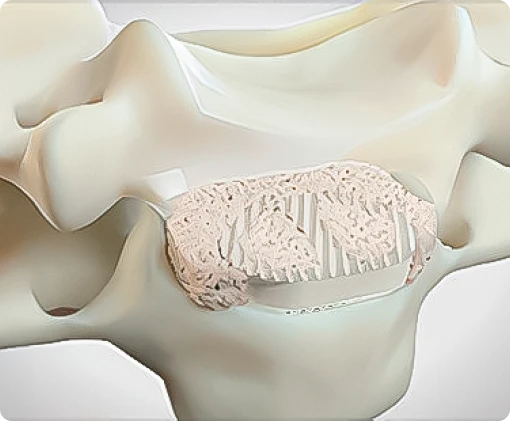

- Cirurgias da coluna e Neuro

- Preenchimento das cavidades ósseas